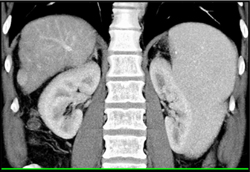

Unusual Liver Abscess